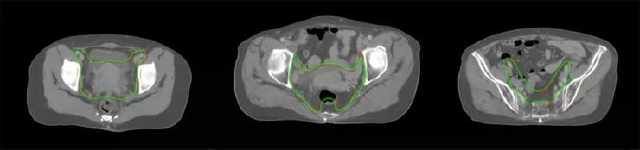

在苏州大学附属第一医院里,联影智能与该院展开了基于uAI放疗轮廓勾画软件的宫颈癌靶区自动勾画研究。

(绿线:自动勾画效果 红线:医师手动勾画效果)

医师手动勾画时长约在数十分钟至一小时,且低年资医师手动勾画时长明显高于高年资医师,而uAI放疗轮廓勾画软件可实现亚秒级智能分割靶区——全盆腔淋巴引流区和宫旁区域,经医师检查确认后到勾画完成只需2-3分钟。